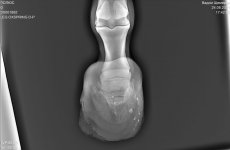

На рентгеновских снимках выявлено:

1) остеохондроз и чип в области путового сустава правой грудной конечности.

2) Старый перелом и изменение конфигурации края челночной кости с переостальной реакцией этого края.